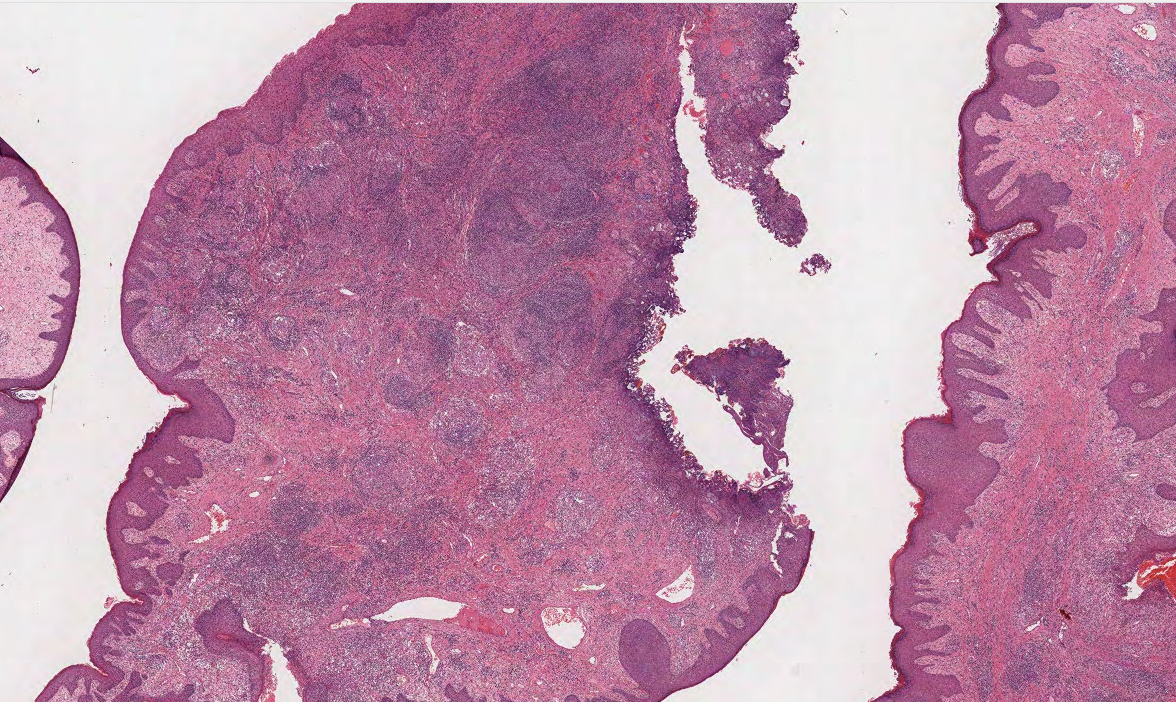

39M anal biopsy

dx

A

Dx: Crohn’s disease.

Exclude infectious processes

The section reveals acanthosis and hyperkeratosis affecting the squamous epithelium, but there is also focal ulceration as well as prominent inflammation within the subepithelial tissues. The inflammatory process includes numerous non-caseating epithelioid granulomas together with a predominantly lymphocytic inflammatory infiltrate elsewhere, with the formation of lymphoid aggregates. In some areas there are also sheets of histiocytes intermingled with the lymphocytes, without obvious circumscribed granuloma formation. Areas of collagenous fibrosis are also evident within the subepithelial zone. The appearances conform to those of chronic and active granulomatous inflammation with focal ulceration of the squamous epithelium, highly characteristic of Crohn’s disease with anal/perianal involvement.